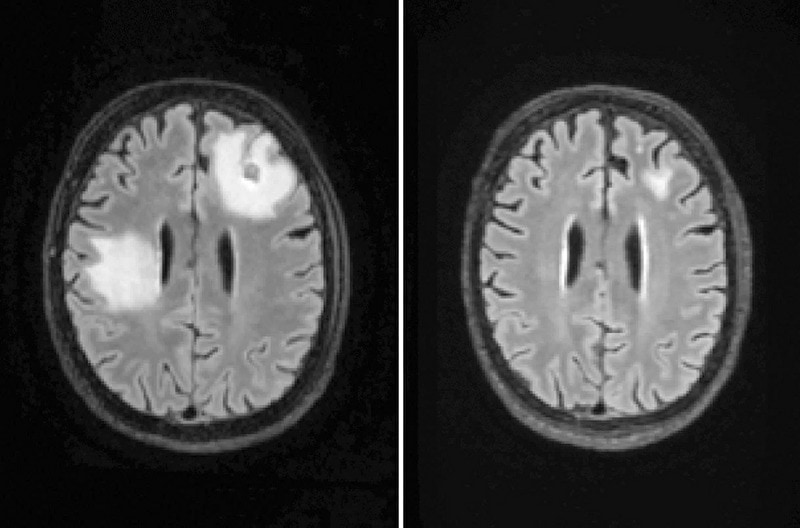

gif_animation アメリカではニュースで報道される事も多いという「脳食いアメーバ」こと「ネグレリア・フォーレリ」に感染した人々の画像や脳画像のまとめギャラリー。このアメーバが一次性アメーバ性髄膜脳炎(PAM)を引き起こした場合、致死率はほぼ100%だと言われている。感染経路は世界中に温かい淡水で、身近な所では「水道水で鼻洗浄」をした女性が亡くなった事例などがある。[13]images